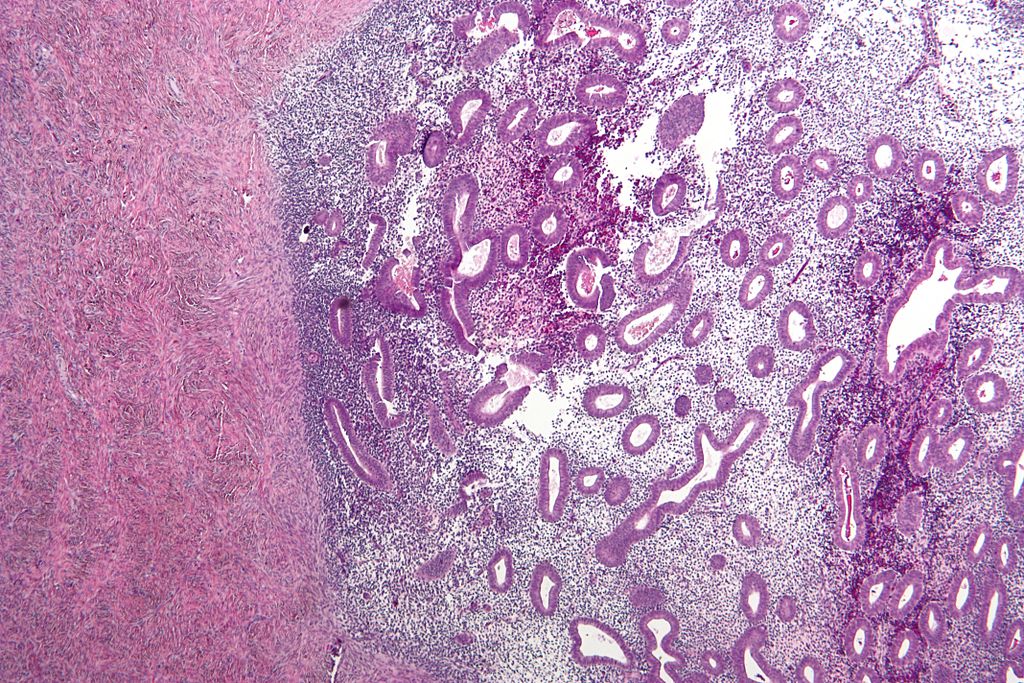

Dezvoltarea acestor celule care sunt plasate greșit duce la apariția unor țesuturi sau leziuni caracteristice endometriozei. Excrescențele endometriale sunt albe, roșii, maronii și sunt depistate mai ales la femeile cu vârsta peste 30 de ani. Ele însă apar chiar înainte de naștere, sunt mici și nu au un colorit închis.

Cavitatea pelvină și peritoneală a femeii trebuie examinată laparascopic de către medic pentru depistarea unor eventuale leziuni endometriale și apoi pentru înlăturarea lor. Indentificarea se face de către medic, iar examenul de laborator pe mostră și biopsia au un rol important în stabilirea diagnosticului. Din păcate mulți chirurgi îndepărtează doar leziunile endometriale tipice care sunt maronii sau negre și astfel multe paciente ajung să sufere după un timp de recidive ale bolii. Dacă se elimină leziunile tipice și atipice se poate ajunge la vindecare în 75% din cazuri.

Endometrioza poate fi asociată cu infertilitatea dar nu este strict cauza acesteia. Țesutul endometrial se poate răspândi și în afara cavității uterine, pe ovare, în vezica urinară, în trompele lui Fallopio, în peritoneu sau membrana pereților cavității abdominale, în musculatura uterului și în intestine.